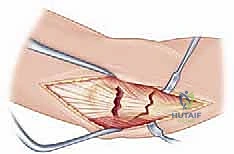

- Identify Landmarks: Palpate the subcutaneous border of the ulna. Medially, identify the robust fascia of the flexor carpi ulnaris (FCU) muscle. Laterally, locate the anconeus muscle, which originates from the lateral epicondyle of the humerus and inserts onto the lateral surface of the olecranon and proximal ulna.

- Develop the Interval: The internervous plane we utilize is between the flexor carpi ulnaris (FCU) medially and the anconeus muscle laterally.

- Anatomy Pearl: The FCU is innervated by the ulnar nerve, while the anconeus is innervated by the radial nerve (via its deep branch, the posterior interosseous nerve). This internervous plane allows us to access the ulna without violating muscle bellies or major neurovascular structures.

- Carefully incise the deep fascia along the subcutaneous border of the ulna. Using blunt dissection with scissors (e.g., Metzenbaum) or a Cobb elevator, gently separate the FCU from the anconeus, reflecting them to expose the ulnar shaft and fracture fragments.

TECH FIG 1 • B. Deep surgical interval uses the internervous plane between the anconeus and flexor carpi ulnaris.

3. Extent of Exposure: The amount of dissection required is dictated by the specific fracture pattern and the type of fixation we plan to use. For a simple diaphyseal fracture, minimal exposure may suffice. For comminuted fractures or those extending proximally, more extensive subperiosteal elevation may be necessary.